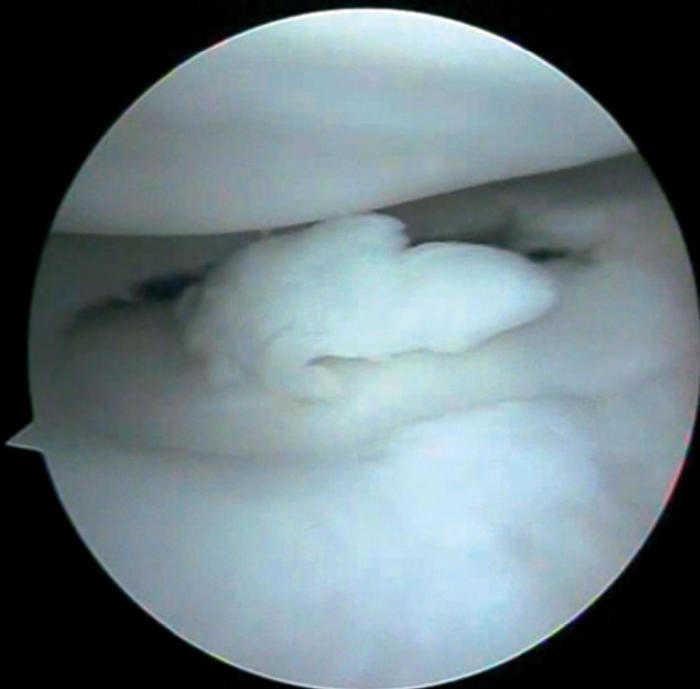

Figura 2 Artroscopia. Cuerpos libres articulares en receso articular interno.

Se practica artroscopia, en la que se observan (figs. 2, 4, 6-8):

• Múltiples fragmentos condrales libres de bordes agudos, que se identifican como recientes y de bordes redondeados que se catalogan como antiguos.

• Resto de estructuras intraarticulares íntegras.

• Se procede a la exéresis de los cuerpos libres y a la regularización de la lesión condral seguida de estabilización por vaporización.